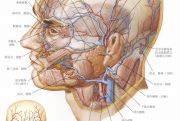

| 2021年7月26日 (一) 20:01 | 面静脉.jpg (文件) |  |

164 KB | 77921020 | Uploaded with SimpleBatchUpload | 3 |